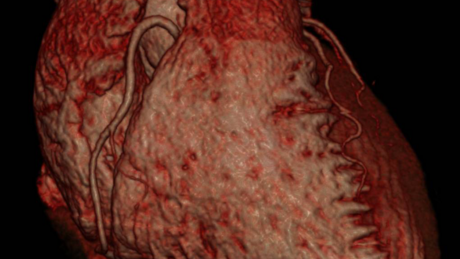

Bild 1: Dreidimensionale Darstellung des Herzens, die Herzkranzgefäße kommen unauffällig zur Darstellung

Bild 2: Vordere Herzkranzarterie des gleichen Patienten in einem speziell rekonstruierten Schichtverfahren